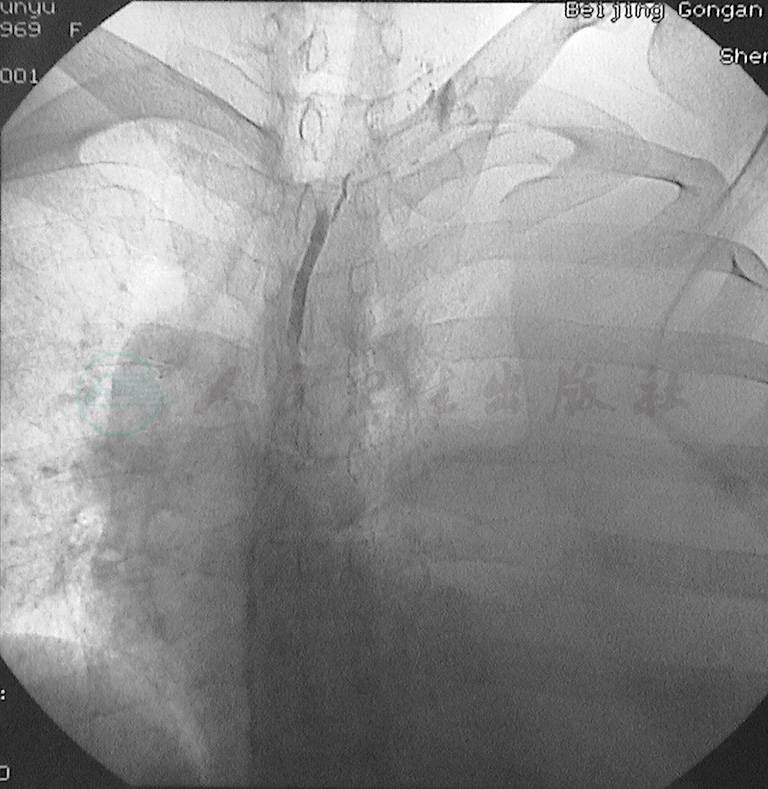

2.乳糜瘘发生在乳糜池(图2)。

图2直接淋巴管造影显示不同时间所拍摄的乳糜池瘘的影像